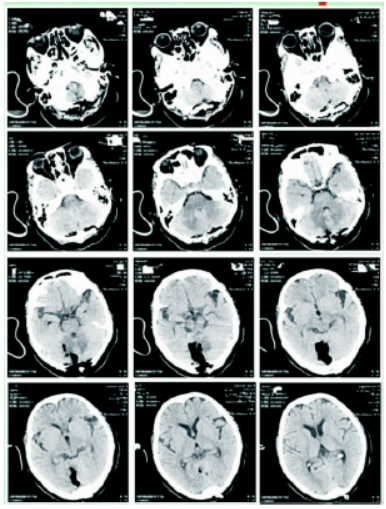

1588559034548106.png

图4 患者出院前复查

1588559047858340.png

图5 ①CD3+;②LCA+;③CK-;④GFAP-;⑤CD20-;⑥ki-67:60%;⑦⑧⑨HE染色胞+、CD1α-(图5)。